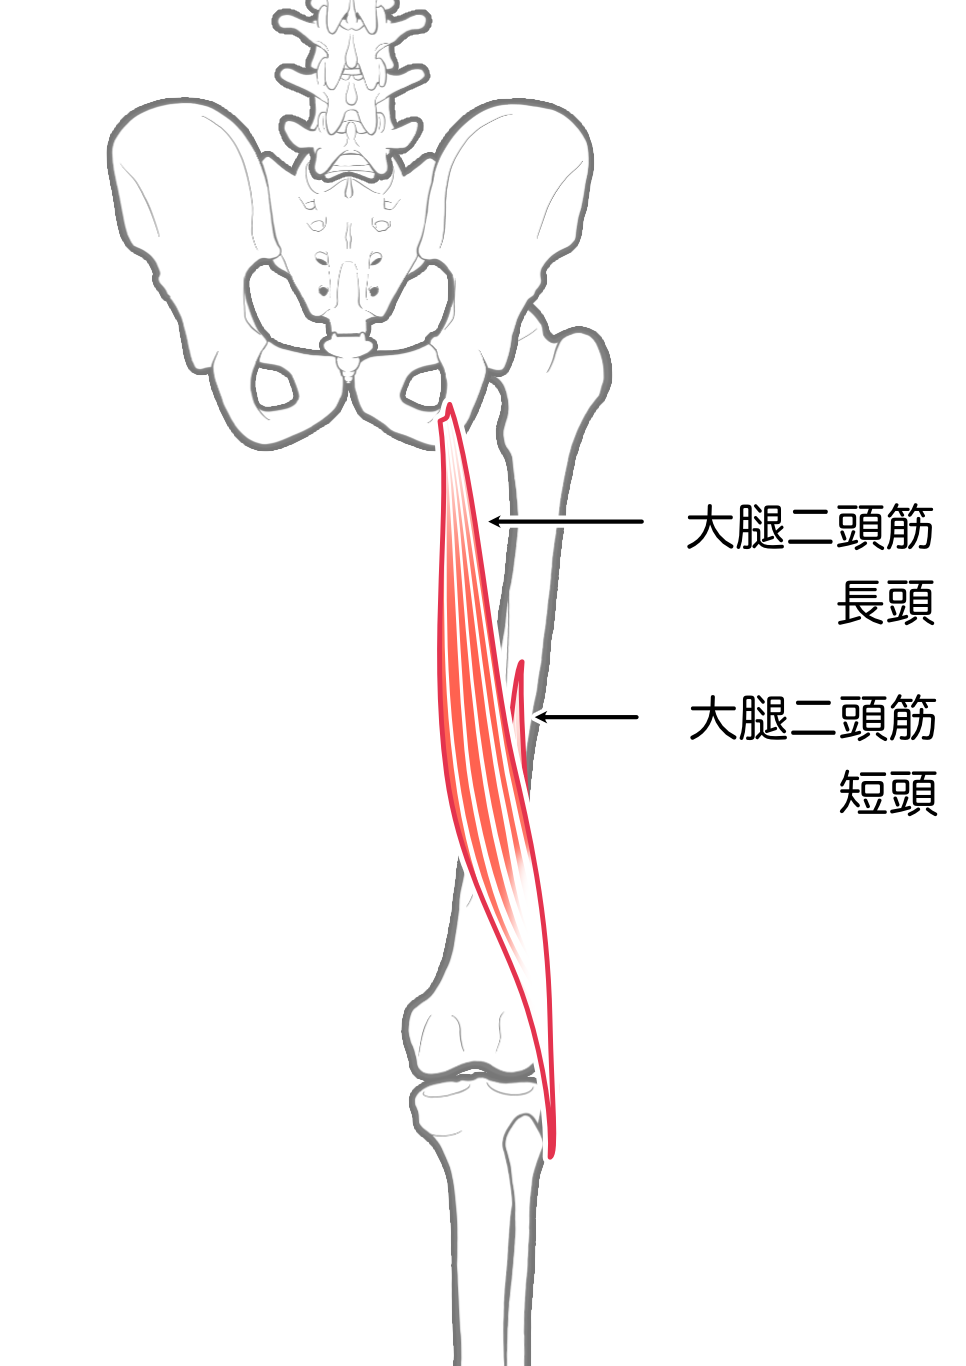

大腿二頭筋

| 起始 | 長頭-坐骨結節 短頭-大腿骨粗線 |

| 停止 | 腓骨頭,脛骨外側顆 |

| 神経 | 長頭-脛骨神経L5-S2 短頭-腓骨神経L5-S1 |

| 作用 | 膝関節屈曲,外旋 |